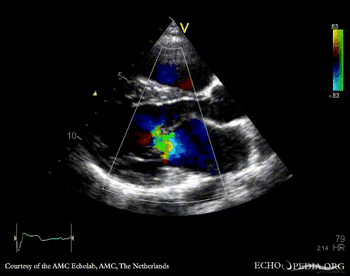

| PLAX: color doppler, mitral regurgitation